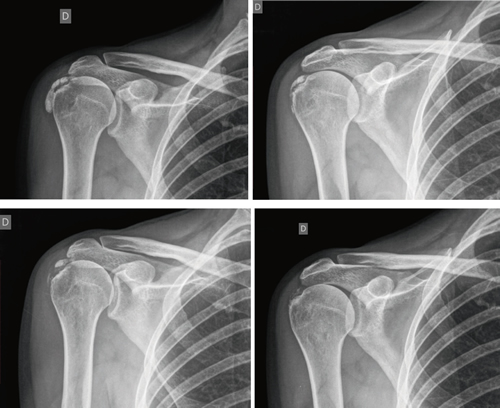

Figure 1

Figure 2

Table I

Figure 3

Figure 4

Figure 5

Figure 6